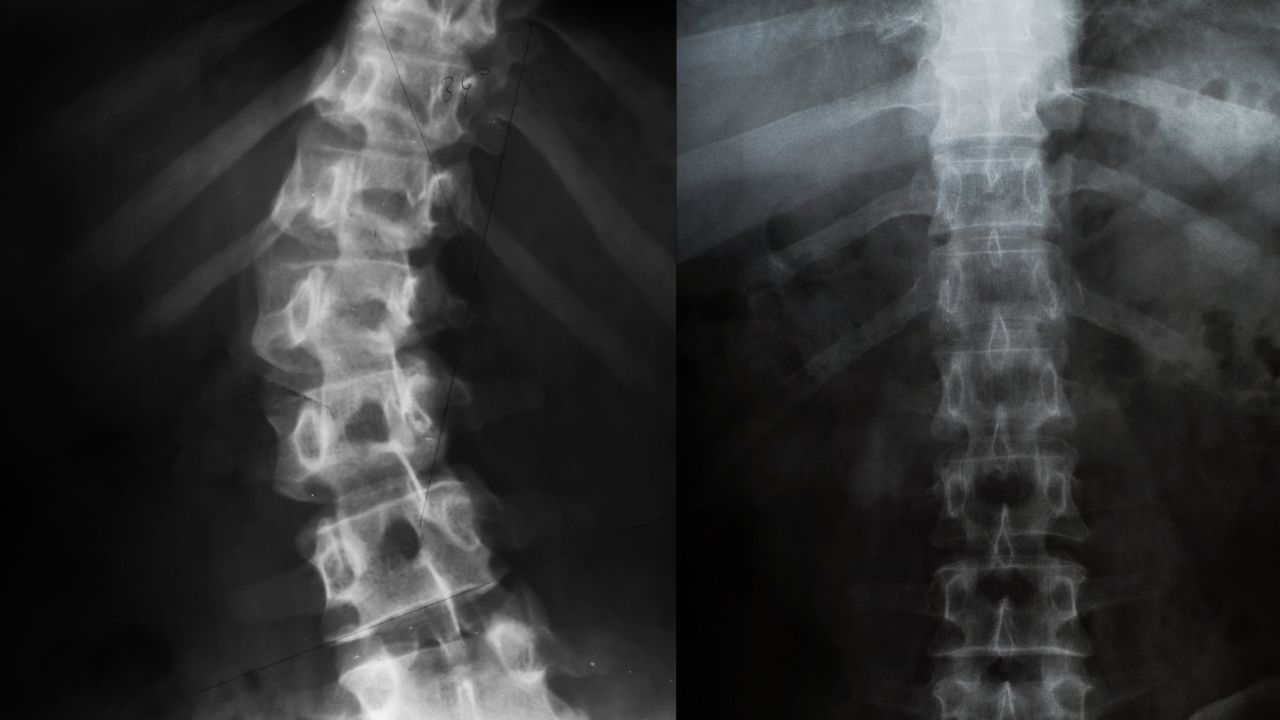

The state has officially included corrective surgeries for spine deformities like scoliosis (sideways curvature of the spine), kyphosis (abnormal forward rounding of the spine), and lordosis (excessive inward curvature of the lower back) under the Ayushman Bharat – Arogya Karnataka Yojana (AB-ArK).

Scoliosis, a condition where the spine curves abnormally, can cause chronic pain, breathing difficulties, and severe physical deformities if left untreated.

Speaking to South First, Dr Manoj Kumar, leading orthopaedic surgeon, Dean and Director of Sri Atal Bihari Vajpayee Medical College and Research Institution (formerly known as Bowring Hospital), explains that “the spine curves sideways by more than 10 degrees, affects around 3.1 percent of children and adolescents worldwide. It can be congenital (present from birth) or idiopathic (unknown cause, often seen in adolescents).”

The surgery, according to doctors, most commonly involves spinal fusion. Here two or more vertebrae are fused together using bone grafts, screws, rods and hooks to correct and stabilise the spine.

Dr Manoj says the surgery can take up to four to eight hours, depending on the severity of the curve and patient’s condition. “Nearly 20-22 screws will have to be used. It is as complex as a cochlear implant surgery. But if done by a trained spine surgeon the surgery is normally safe and also successful.”